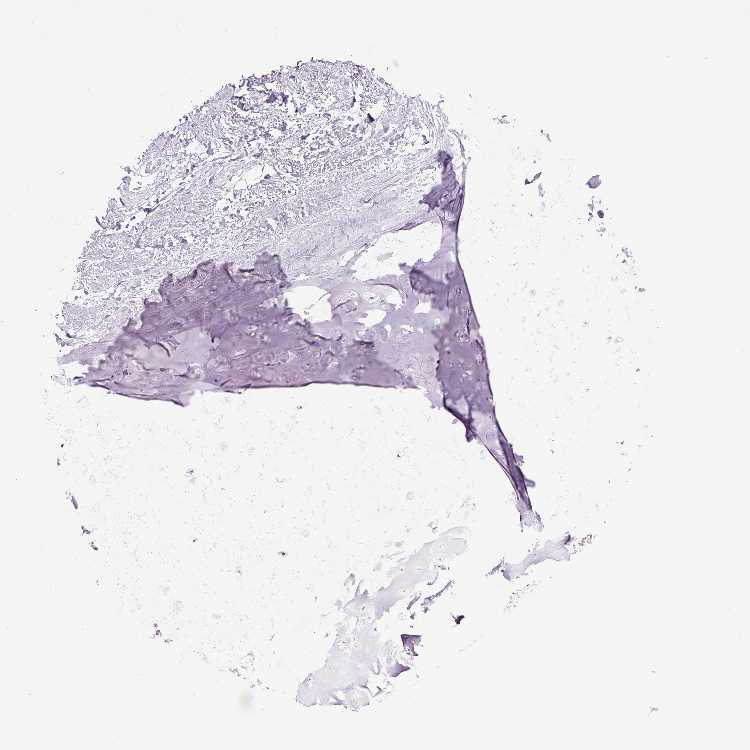

SOFT TISSUE 1 - Antibody stainingi

Antibody staining in the annotated cell types in the current human tissue is reported as not detected, low, medium, or high, based on conventional immunohistochemistry profiling in selected tissues. This score is based on the combination of the staining intensity and fraction of stained cells.

Each image is clickable and will lead to virtual microscopy that enables deeper exploration of all samples and also displays staining intensity scores, fraction scores and subcellular localization as well as patient and tissue information for each sample.

Antibody HPA036705Antibody CAB025834

Fibroblasts Not detectedNot detected

Peripheral nerve Not detectedNot detected